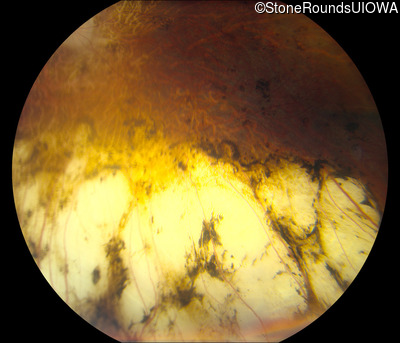

Fundus Photography - Left - 20/200 sc

Exemplar